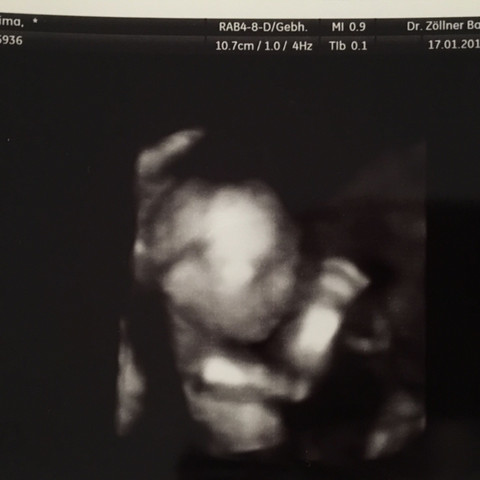

Hallo zusammen ) Zu welchem Geschlecht tendiert ihr anhand des Fotos?. SSW bereits das Geschlecht Ihres Babys erkennen Um Abtreibungen auf Grund eines „falschen“ Geschlechts zu vermeiden ist es dem Arzt untersagt das Geschlecht des Babys vor Ablauf der 12 Schwangerschaftswoche mitzuteilen (§15 Gendiagnostikgesetz). So findest Du eine Hebamme Auch Papa sucht die Geburtsklinik aus Alle Infos zur 15 Schwangerschaftswoche gibt es hier.

15 SSW Erkennt ihr das Geschlecht?. Per Gesetz (§ 15 Gendiagnostikgesetz) darf deine Frauenärztin dich mit deiner Einwilligung erst zum Ablauf der 12 Schwangerschaftswoche über das Geschlecht deines Kindes informieren Auch zu diesem Zeitpunkt ist die Fehlerquote noch recht hoch Die Wahrscheinlichkeit, dass deine Ärztin richtig liegt, liegt in der 13 Woche bei 80% Bei den. 15 SSW – Wichtiges auf einen Blick Du befindest Dich jetzt in der 15 SSW (140 bis 146) Dein Baby ist jetzt etwa 8 Zentimeter groß;.

Ihr seht das Kind von unten Ich bin jetzt in der 17 Woche und das Foto ist aus der 15 Grüße Hen BabyCenter. 6 Oktober 14 um 2247 Letzte Antwort 7 Oktober 14 um 19 Hallo war heute beim Frauenarzt und habe ein neues ultraschallbild erhalten Da wo der Pfeil ist ist das Geschlecht?. Home / Forum / Schwangerschaft & Kinderwunsch / 153 ssw outing?.